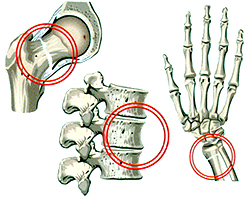

По данным современной травматологии риск возникновения переломов увеличивается пропорционально снижению плотности костной ткани. При снижении плотности костей на 10% частота переломов возрастает в 2-3 раза. Остеопороз в первую очередь поражает кости с преобладанием губчатого вещества (позвонки, кости предплечья в области лучезапястного сустава), поэтому типичным осложнением заболевания являются переломы тел позвонков и лучевой кости в типичном месте.

Самым значимым проявлением остеопороза являются переломы (обычно – тел позвонков или лучевой кости). Особую опасность представляют переломы шейки бедра, которые в 20-25% случаев становятся причиной смерти больных в течение первого полугодия после травмы, а в 40-45% приводят к наступлению тяжелой инвалидности.